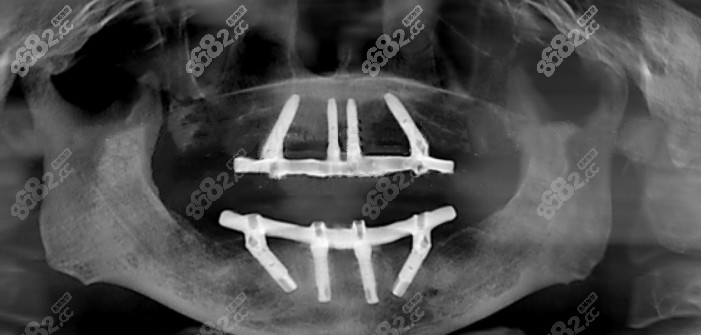

張叔叔做完全口種植牙的片子▼